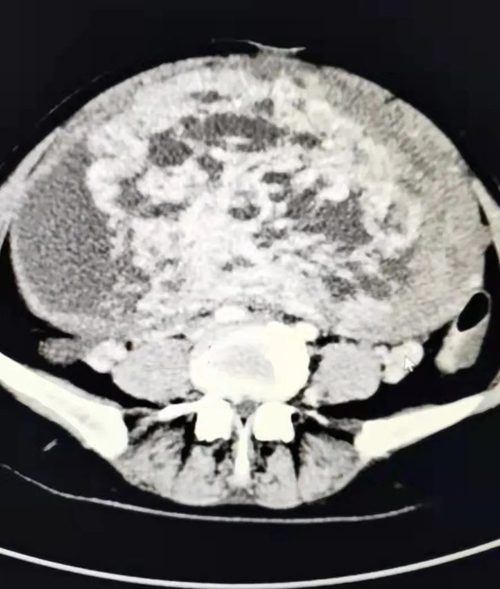

患者女,50歲,平素月經(jīng)規(guī)律,無痛經(jīng),無異常陰道流血,近半月來出現(xiàn)無明顯誘因腹脹、輕度腹疼、小便頻,來我院消化內(nèi)科就診,發(fā)現(xiàn)腹部異常膨隆,彩超見一巨大囊實(shí)性包塊,較大切面范圍約22.7*18.1CM,部分切面與宮底肌層關(guān)系密切,其內(nèi)囊性部分呈多房樣改變,實(shí)性部分血流信號(hào)豐富,CA125 98.85U/ml,以“盆腔包塊瘤”收入婦二科。

3月1日下午15:30分,患者被推進(jìn)手術(shù)室。按照術(shù)前制定的麻醉方案,麻醉醫(yī)師方軍為患者進(jìn)行了橈動(dòng)脈穿刺和中心靜脈置管,實(shí)時(shí)監(jiān)測(cè)患者血壓變化,保證輸液通暢,確?;颊呤中g(shù)中生命體征平穩(wěn)。手術(shù)護(hù)士長(zhǎng)安排了經(jīng)驗(yàn)豐富的護(hù)士甘瑾、邱靜靜和張兆霞配合手術(shù)。在麻醉科及手術(shù)室的支持配合下,手術(shù)有條不紊地進(jìn)行。打開腹腔后,見子宮異常膨隆,占據(jù)整個(gè)腹腔、盆腔,緩慢吸引出囊腔內(nèi)囊液約1500ml,將子宮搬出腹腔,沙袋壓迫上腹部,避免血壓驟降,手術(shù)歷經(jīng)2個(gè)小時(shí),完整切除了這一罕見的巨大肌瘤的子宮。術(shù)中快速病理為漿膜下平滑肌瘤,伴水腫囊性變。術(shù)后患者蘇醒,安返病房。